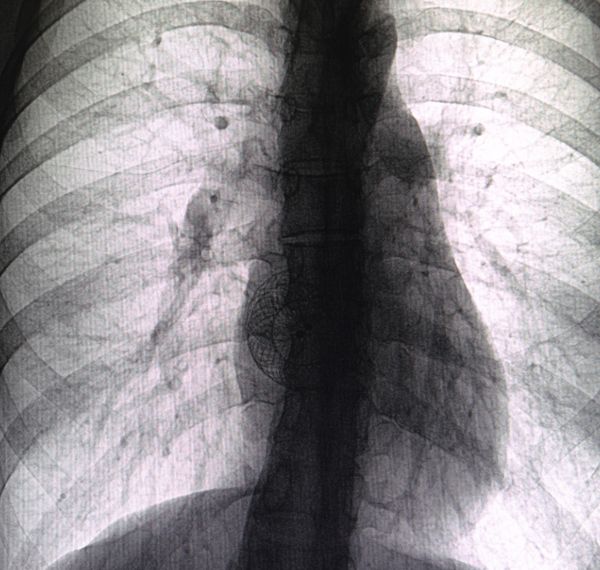

Pacemaker Implantation

Implanting a device to stabilize irregular or slow heartbeats.

Who it’s for: Individuals with arrhythmias or heart block.

Benefits: Maintains a steady heartbeat, reduces fatigue, and enhances energy and life quality.